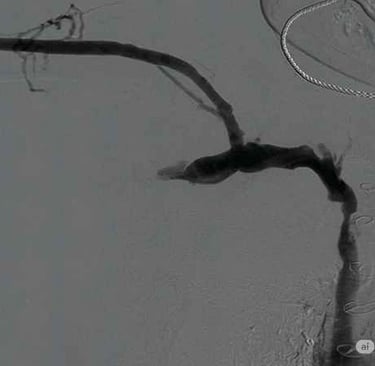

Flebografía de vena cava superior estenótica

Flebografía de la vena ácigos en presencia de estenosis cavoatrial

Estenosis de la vena yugular con dilatación de sus efluentes